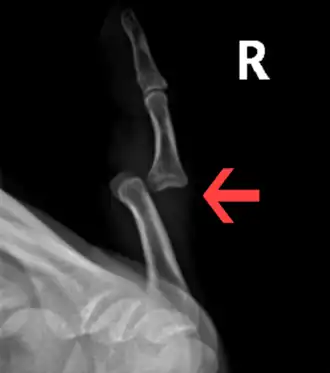

Dislocation of the left index finger -

Radiograph of right fifth phalanx bone dislocation -

Radiograph of left index finger dislocation

Radiograph of right fifth phalanx dislocation resulting from bicycle accident -

Right fifth phalanx dislocation resulting from bicycle accident